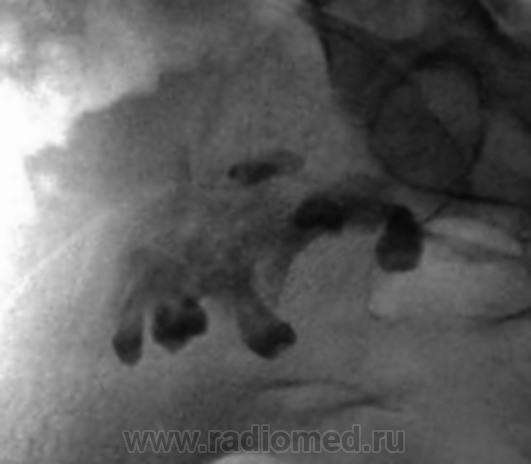

Наблюдение Виктора Григорьевича. ТЕРАТОМА или "Зубы в малом тазу".

Чкстно говоря - я тоже такое чудо увидел первый раз за 25 лет работы в радиологии...сначала была обзорная рентгеноскопия брюшной полости, потом - ирригоскопия, наблюдалось легкое оттеснение сигмовидной, прямой и слепой кишки, при случае постараюсь и эти снимки предоставить.

Это не круто, это навевает на мысль - на возможность появления новой профессии (в плане доступа) - "проктолог - стоматолог", зубы-то четко видны, а мы-то, знаем как болят зубы? А "там-то", их, пускай, и "заблудшие", но родственники (по зародышевым листкам).